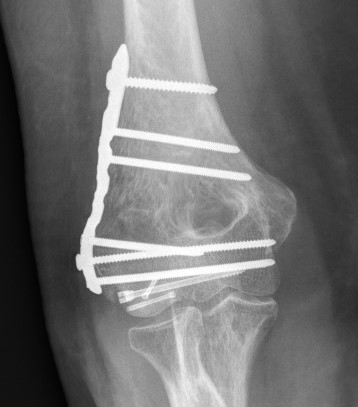

ORIF with PA screws and posterolateral plate

Large capitellum fracture / lateral column ORIF with plate and screws

Comminuted coronal shear fracture in elderly patient treated with distal humerus replacement